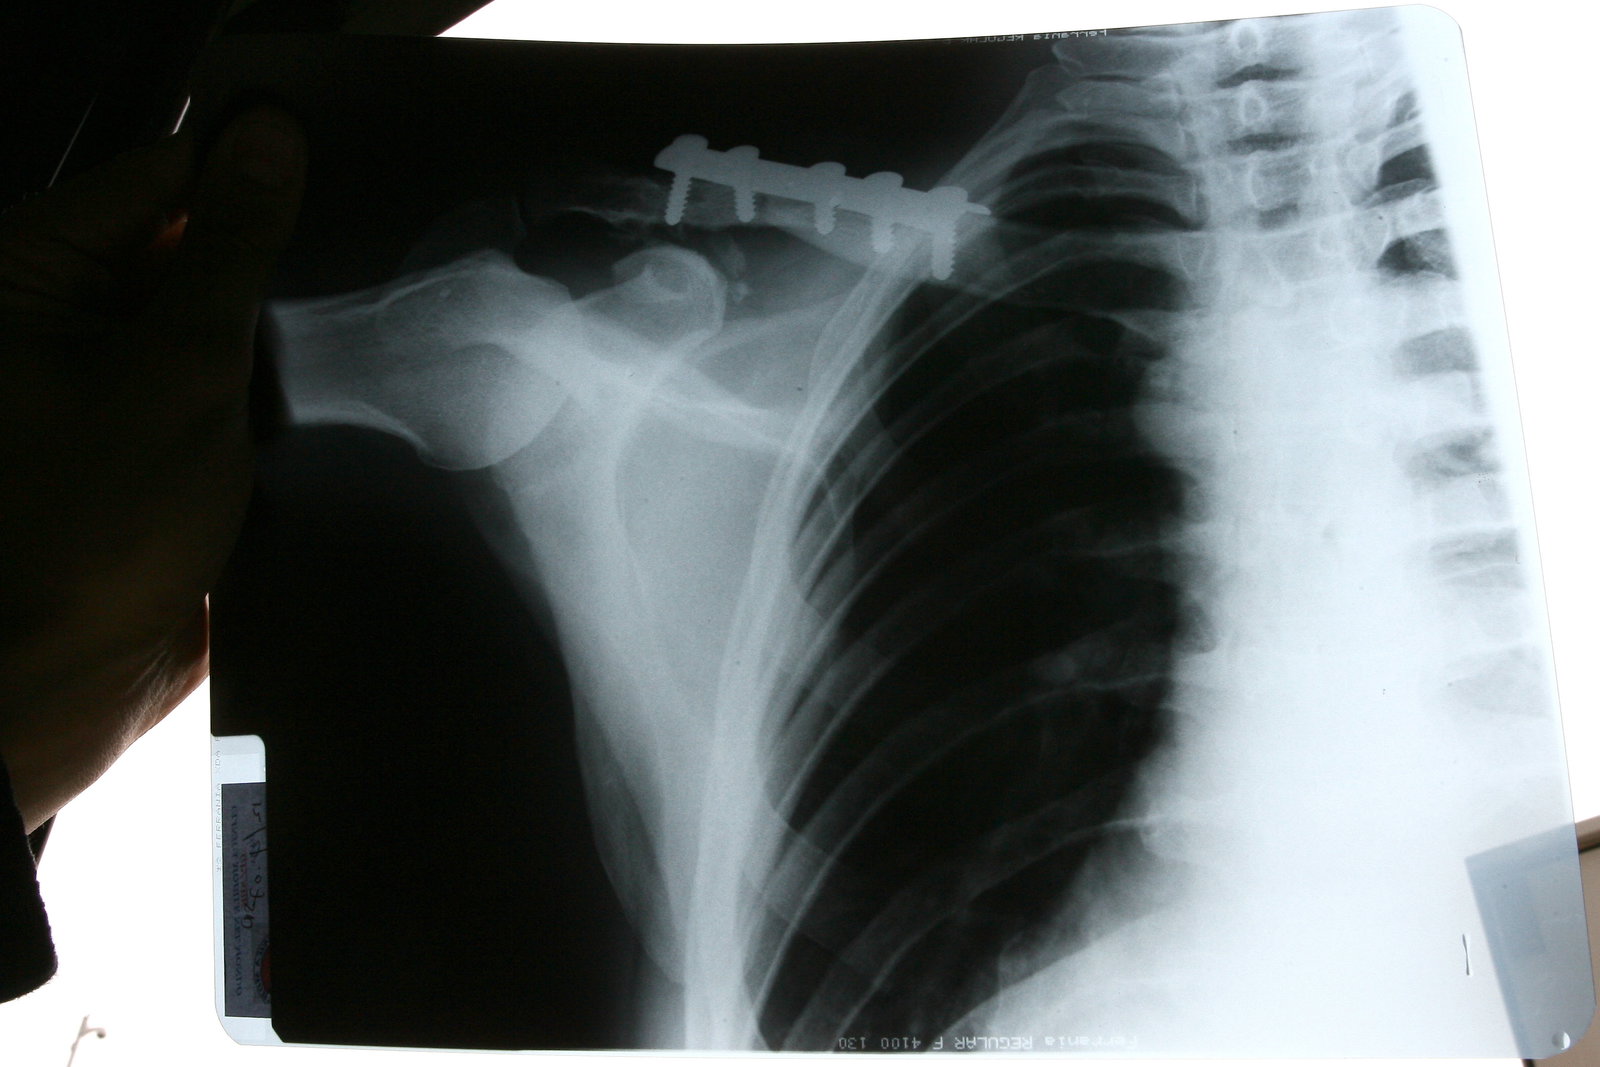

"My season so far has not gone the way I expected - too many crashes!" admitted Yuki. "At Donington, I had another crash [in practice] and, because I knocked myself out for a few minutes, the doctors would not let me race. Also, a few days later my ribs felt a bit sore. At the moment, I have missed four races and I don't like that. Practice and testing is OK, but I am missing race action.

"Valencia has mixed memories for me, but what is important is what happens next weekend. I will make a check on how my ribs are before I decide to race, because I know Valencia is a very physical track and, if my ribs are a problem, it may be not possible for me to race. We shall see what happens when we get there," he declared.